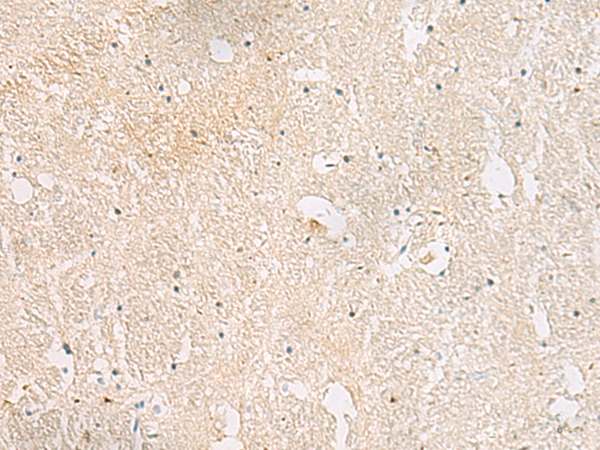

IHC positive control: |

Human brain |

IHC Recommend dilution: |

20-100 |